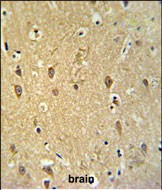

- GPR17 Antibody (Center) (Cat. #P30554) IHC analysis in formalin fixed and paraffin embedded brain tissue followed by peroxidase conjugation of the secondary antibody and DAB staining. This data demonstrates the use of the GPR17 Antibody (Center) for immunohistochemistry. Clinical relevance has not been evaluated.